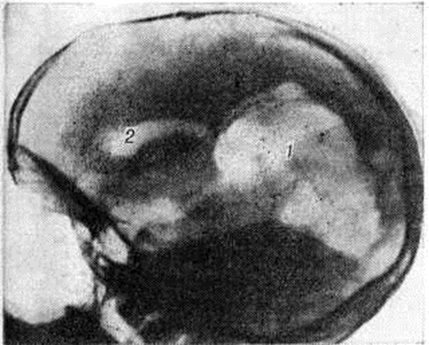

Различают истинную и ложную Порэнцефалия При истинной Порэнцефалия кисты могут сообщаться с желудочками мозга, являясь как бы их дивертикулами, иногда распространяющимися до наружной поверхности полушария головного мозга (рисунок 1). Реже кистозные полости с желудочками мозга не сообщаются. Величина кист очень вариабельна; некоторые из них иногда могут занимать половину и более половины полушария головного мозга, Внутренняя поверхность кисты чаще всего гладкая, выстлана эпендимоподобной оболочкой. Если киста сообщается с желудочками мозга, она содержит цереброспинальную жидкость, а если не сообщается — кистозную желтоватую жидкость с большим количеством белка, Микроскопически в стенке кисты выявляются участки, образованные гетеротопированной, имеющей неправильное строение корой головного мозга. В стенках кист иногда обнаруживают гемоглобиногенную пигментацию (следы очаговых кровоизлияний) и мелкие аноксические некрозы. Боковые желудочки часто имеют неправильную форму и расширены, особенно в области прилегания порэнцефалической кисты. Извилины полушарий головного мозга радиально погружены в направлении кисты, а иногда в этой области совсем отсутствуют и на их месте имеется лишь тонкая пластинка из мозгового вещества и мягкрй оболочки головного мозга, кратерообразно западающая при вскрытии полости. Гистологический изменения в ближайших к кисте извилинах головного мозга характеризуются выраженным разрежением ганглиозных клеток и неправильной ориентировкой клеточных слоев. В мягкой оболочке головного мозга отмечаются очаговые некрозы. Эти изменения указывают на раннее возникновение истинной Порэнцефалия

Порэнцефалия устанавливают на основании признаков органического поражения головного мозга и данных пневмоэнцефалографического исследования (смотри полный свод знаний: Пневмоэнцефалография). При истинной Порэнцефалия с помощью пневмоэнцефалографии выявляют кистозные полости, сообщающиеся с желудочками мозга, при этом желудочки обычно подтянуты к области дефекта ткани мозга (рисунок 3). Соустье между кистой и желудочком мозга определяется на пневмоэнцефалограмме, если диаметр его составляет не менее 2 миллиметров.: Расположенные в глубине мозга небольшие полости, сообщающиеся с желудочком мозга очень узким ходом, представлены на рентгенограммах как отшнурованные кистозные полости.